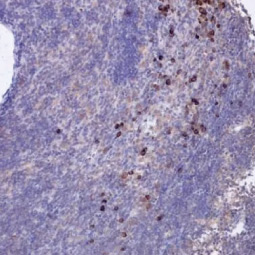

| RAS (G12D Mutant) antibody [HL10] (GTX635362) ![]() ![]() ![]() ![]() | PD-L1 antibody [HL1041] (GTX635975) ![]() ![]() ![]() ![]() ![]() ![]() | 53BP1 antibody [HL275] (GTX635479) ![]() ![]() ![]() ![]() |